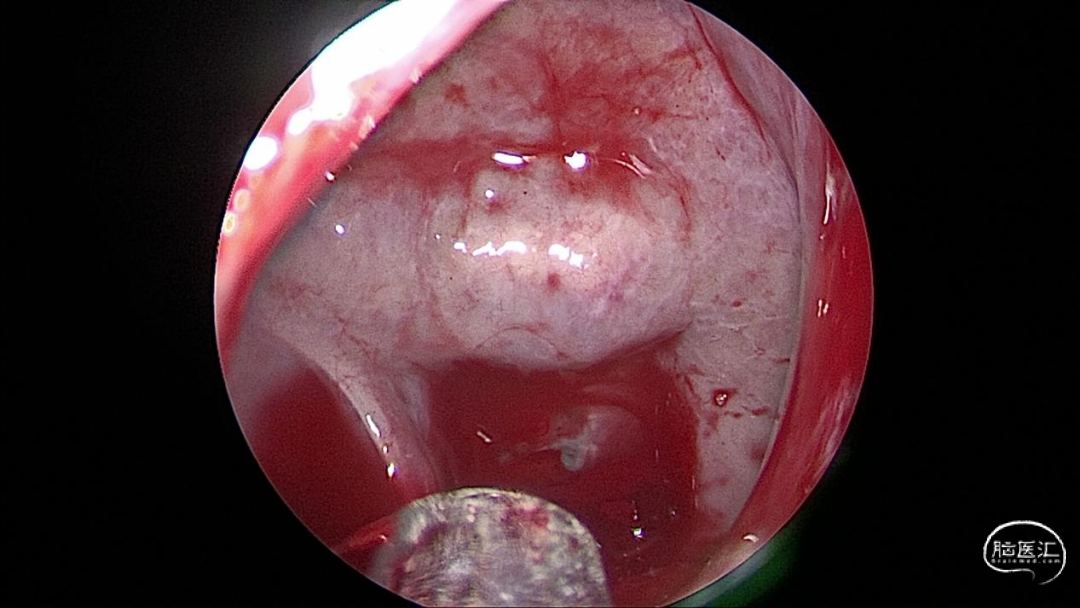

手术照片

至此,我们基本可以判断,漏口位于蝶窦腔内,而且斜坡骨质缺损处嫌疑最大。那实行了神经内镜下探查+脑脊液漏修补术。